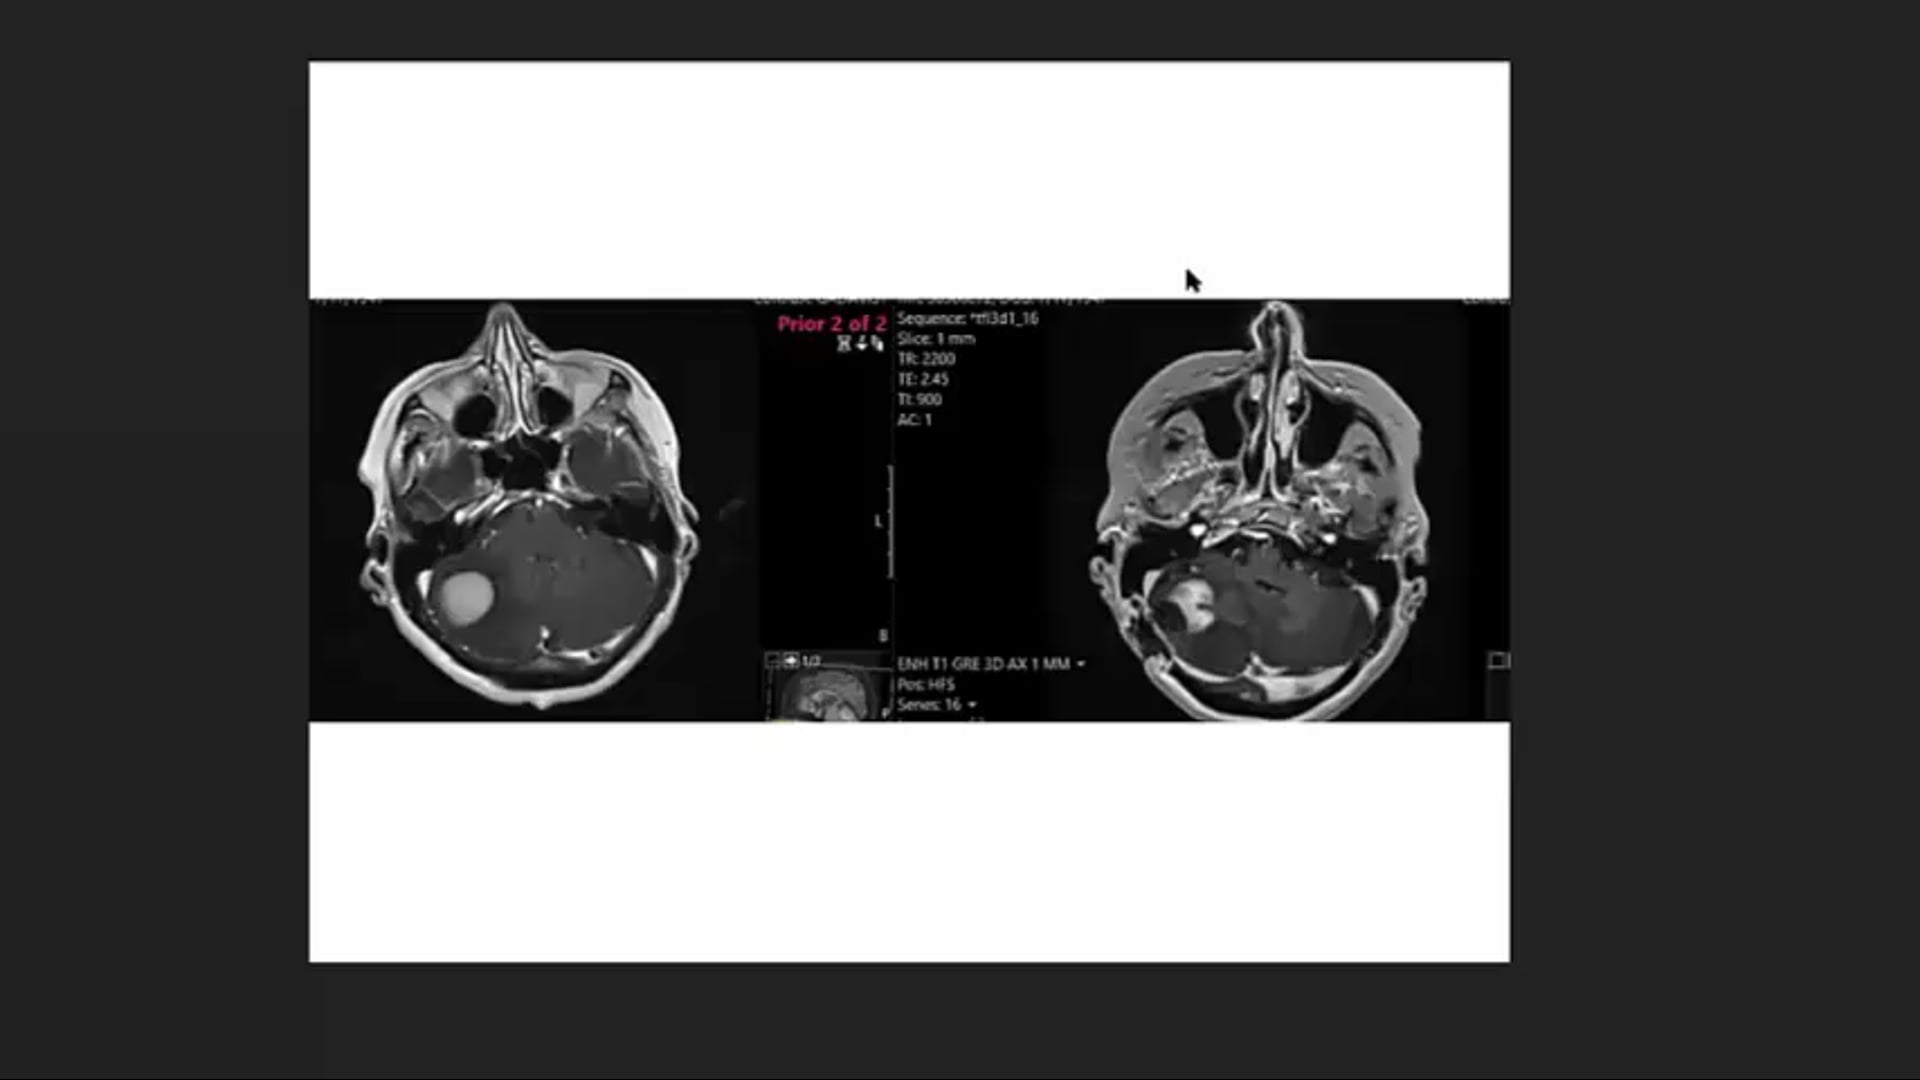

Orbital Lymphoma